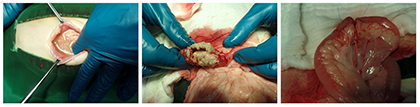

Peritoneocentesis를 통해 채취된 복수를 분석한 결과, bacterial peritonitis로 진단됐다[그림 2]. 복수를 배양한 결과 병원체는 Escherichia coli가 확인 되었으며, 항생제 감수성 결과에서는 대부분의 항생제가 감수성 있는 것으로 확인 됐다.

검사 결과 등을 통해서 장 천공에 의한 bacterial peritonitis로 확인되어 천공 부위의 확인 및 교정을 위해 진단적 개복술을 실시했다. 개복 시에 복강 내 염증성 복수가 관찰되었고, 복강 내 장기들이 염증으로 인해 유착되어 있는 것을 확인했다.

공장 부위의 확인 시에 천공된 부위를 확인하고, 천공 부위 절제 후에 정상 공장 부위의 장문합술을 실시했다. 천공의 원인이 될만한 이물 등은 발견되지 않았다. 여러 번의 복강세척을 실시하고, 복강 내 drain을 장착하여 수술을 완료했다[그림 3].